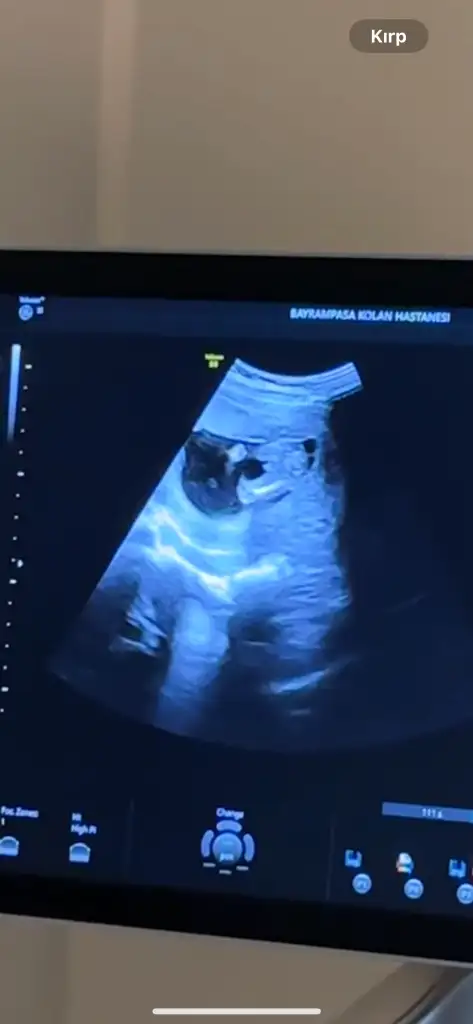

Ultrason resmını at bakalım kuzum,erkek cocugu cok barız bellı oluyor cunkuKızlar teşekkür ederiiimama doktor %80-90 erkek dedi sanırım değişmez?

Ya o kadar saçma foto verdi ki ben video çektirttim ordan kırptım dur. Bak iki bacak arası hahahaUltrason resmını at bakalım kuzum,erkek cocugu cok barız bellı oluyor cunkupipisi varsa erkektır hadı gozun aydın ılk kez yanıldım bu grupta

Erkek benceYa o kadar saçma foto verdi ki ben video çektirttim ordan kırptım dur. Bak iki bacak arası hahaha

Ay bariz erkek bebis herseyi gorunuyoor <3 Tebrik ederimmmmYa o kadar saçma foto verdi ki ben video çektirttim ordan kırptım dur. Bak iki bacak arası hahaha

Ayy değişmez bence çocuğun pipisi ortadaYa o kadar saçma foto verdi ki ben video çektirttim ordan kırptım dur. Bak iki bacak arası hahaha